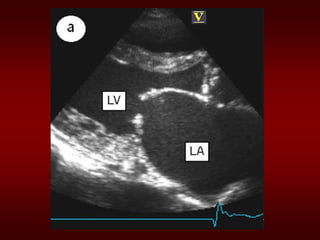

Evaluation of MS

• ECG: may show atrial fibrillation and LA

enlargement

• CXR: LA enlargement and pulmonary

congestion. Occasionally calcified MV

• ECHO: The GOLD STANDARD for

diagnosis. Asses mitral valve mobility,

gradient and mitral valve area